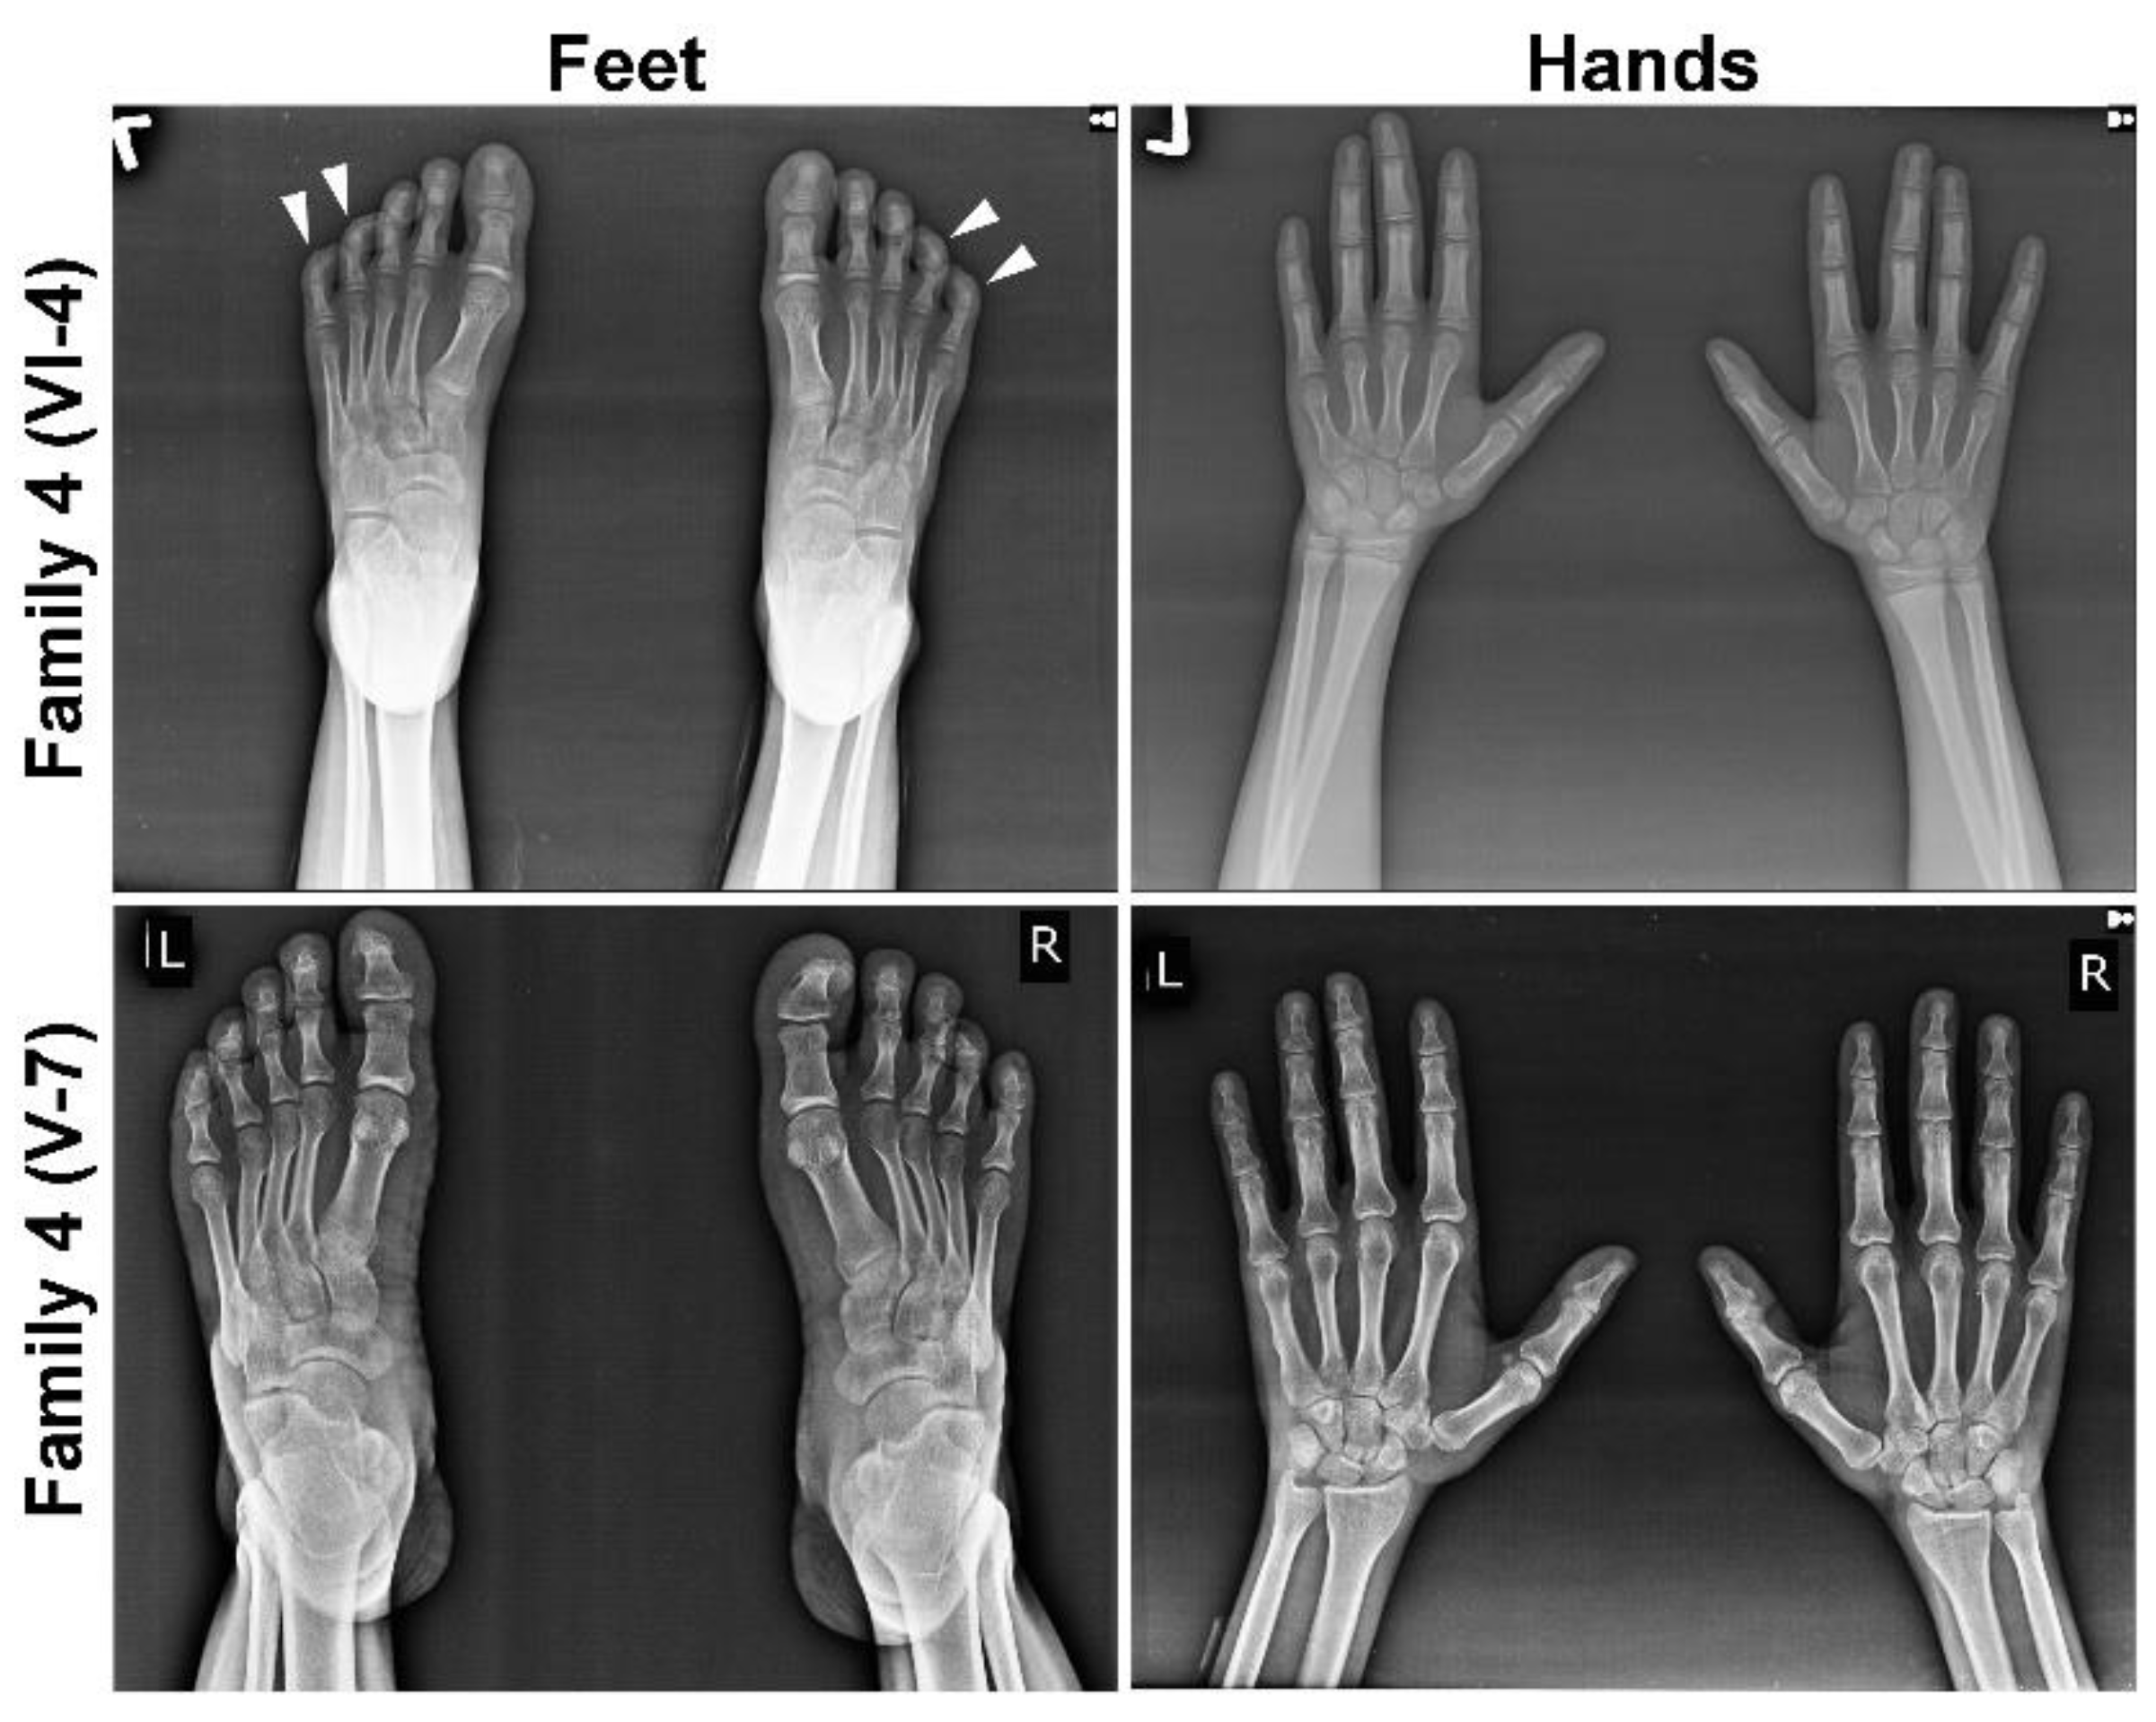

In each MCPH family, we noted microcephaly of varying degree (−9 to −15 SD), slopping forehead and articulation difficulties (Figure 1B and Table 1). Intriguingly, some of the kins showed additional phenotypic features, including joint contractures of both elbows and hands, drooling, a short stature (family 1; V-1 and V-9), seizures, hyperactive locomotion, dwarfism (family 2; V-1 and V-2), seizures, aggressive behavior and severe forms of ID (family 3; IV-1 and IV-2) (Table 1 and Figure 1B). Similarly, patients of family 4 (V-6, V-7 and V-8) and 5 (IV-1 and IV-2) featured Seckel syndrome as indicated by a beaky and protruding nose, hypopigmentation (family 4, V-7 only), malocclusion (family 5, IV-1 only) and short stature (Table 1 and Figure 1B), whereas other affected members of family 4 (VI-2, VI-3 VI-4 and VI-5) also manifested mild ID, drooling, clinodactyly of toes and brachydactyly of fingers and toes evincing MOPDII (Table 1 and Figure 1B). Two patients of family 4, one from each loop, were subjected to radiographic analysis, which indicated bilateral clinodactyly of the 4th and 5th toes only in patient VI-4, manifesting the MOPDII phenotype, and it was absent in patient V-7, showing features of Seckel syndrome (Figure 2).

Figure 2. Radiographic images of selected members of family 4. Radiographs of hands and feet of MOPDII patient VI-4 (upper panel) and Seckel patient V-7 (lower panel). Bilateral clinodactyly of the 4th and 5th toes is seen only in MOPDII patients, indicated by white arrow heads.